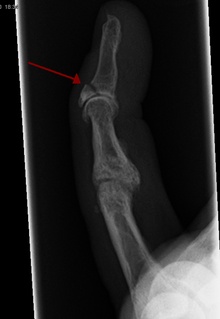

What is an avulsion injury/fracture?

Is where a ligament or tendon that is attached to a bone, pulls a piece of the bone off. Can happen anywhere but most common sites are the finger, ankle, foot and hip.